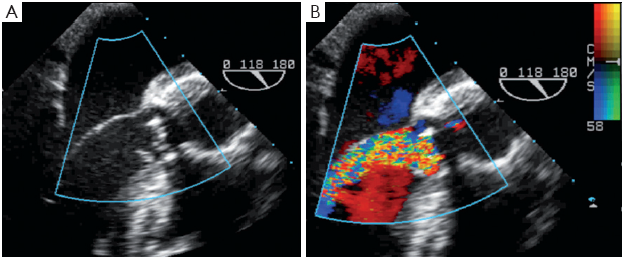

Ventriculo-atrial Defect after Bioprosthetic aortic valve ...

Ventriculo-atrial defect after bioprosthetic aortic valve replacement Jayant S Jainandunsing1, Remco Bergman1, Jacob Wilkens2, Angela Wang3, cal treatment is reserved for treatment of complications due to degenerative disease process or resistant micro-organisms [11]. ... Get Doc